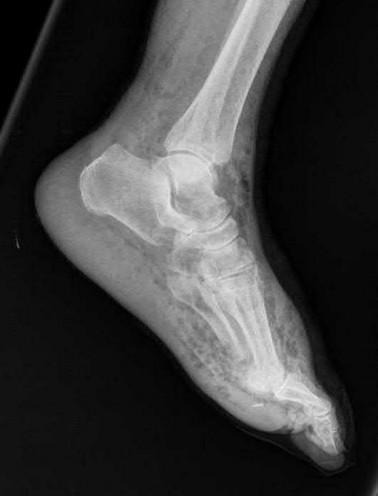

A 64-year-old woman is thrown off a horse, sustaining the injury shown in Figures A and B. She undergoes surgical fixation as seen in Figures C through E. What is the most commonly reported complication of this procedure?

The patient in the scenario has a 2-part proximal humerus fracture treated with a locking plate as seen in Figures A-E. The most common complication with the use of this implant is screw penetration. The terms screw cut out and penetration are often used interchangeably in the literature with cut out appearing more frequently in reports regarding intertrochanteric fractures.

Owsley et al retrospectively reviewed 53 proximal humerus fractures treated with locking plates and the same post-operative protocol. The most common complication was screw cut out or penetration, followed by varus displacement. They concluded that 3 and 4-part fractures in patients over 60 years have a higher incidence of failure.

Agudelo et al retrospectively reviewed 153 patients at a level-one trauma center treated with proximal humerus locking plates, investigating modes of failure for the implant. They determined that varus malreduction (head-shaft angle